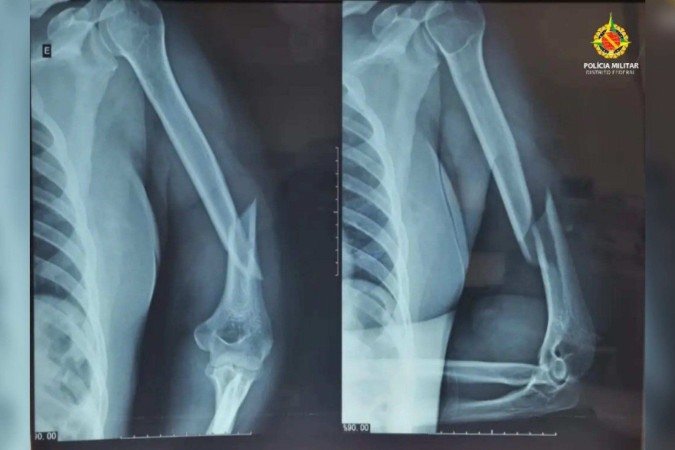

Ao chegarem ao local, os policiais encontraram a vítima com hematomas no rosto, inchaço nos olhos, sangramento nos ouvidos, fratura no úmero e luxação no ombro esquerdo. Segundo o Serviço de Atendimento Móvel de Urgência (Samu), o quadro clínico é compatível com trauma cranioencefálico (TCE).